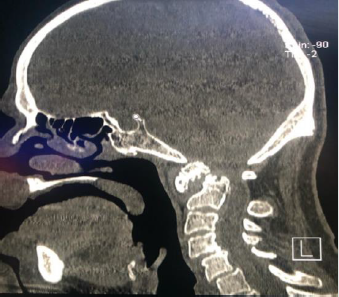

It is a drama film directed by Oliver Nakech and Eric Toledano. Story inspired by the life of a rich Count Phillippe Pozzo di Borgo Author of the book “Le Second Soulffle”. Two characters, totally opposites are a rich, educated and very intolerant Francoiz Cluzet parapejico since 1993 due to a paragliding accident and his relationship with Omar Sy immigrant from Senegal, with criminal record. The high traumatic medullary section (MS)) can lead to a spectrum of neurological problems, including loss of motor and sensory function, bowel and bladder dysfunction, spasticity, neuropathic pain and autonomic dysreflexia. Signs of suspected spinal injury include limb weakness or paralysis, alterations in trunk or limb sensitivity. Hypophonia (difficulty in language issuance), abdominal breathing, hypotension and paradoxical bradycardia, position in flexion of the paresthesia elbows, pain, deformity in the spine and priapism (Figures 2&3).

Figure 4: 68-year-old woman, known with vasculitis and rheumatoid arthritis, C1-C2 dislocation fracture with spinal bulb injury, spondylolysis C4-C5 and C5-C6.